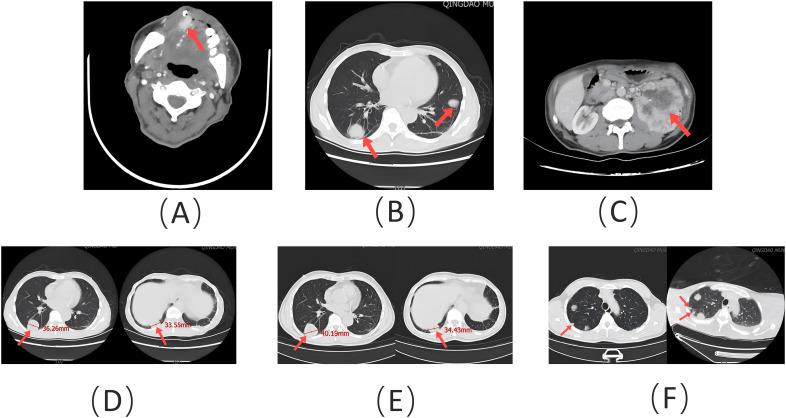

Clear cell renal cell carcinoma (ccRCC) is the most prevalent and lethal subtype of renal cell carcinoma (RCC), characterized by a poor prognosis and a high likelihood of distant metastasis. Nonetheless, metastasis of ccRCC to the tongue remains rare. Diagnosing and planning treatment for patients who initially present with tongue metastasis can be particularly challenging, as few cases have been reported in the literature. We present a case of a 62-year-old man who presented with a painful lump on the right anterior border of his tongue. Histological examination revealed lobulated and nested epithelial cell clusters with moderate dysplasia and frequent mitotic figures within the lamina propria. Immunohistochemistry showed positivity for vimentin, CD10, PAX-8, and epithelial membrane antigen (EMA), but negativity for PAX-2, calponin, S-100 protein, periodic acid-Schiff with diastase (PAS-D), P63, P40, and CK7, confirming the diagnosis of ccRCC metastasis to the tongue. After comprehensive evaluation and multidisciplinary team consultation, the patient underwent cytoreductive nephrectomy (CN), metastasectomy, and targeted therapy. According to the Response Evaluation Criteria in Solid Tumors (RECIST) Version 1.1, the patient maintained stable disease (SD) during systemic treatment. Unfortunately, treatment was discontinued due to adverse drug reactions, and the patient was transitioned to palliative care. His disease progressed to progressive disease (PD), and he ultimately succumbed to systemic infection, with a progression-free survival (PFS) of approximately 15 months. This case highlights the urgent need for improved therapeutic strategies to manage symptoms and prolong survival in patients with this rare metastatic presentation.

透明细胞肾细胞癌(ccRCC)是肾细胞癌(RCC)中最常见且致死性最高的亚型,其特点是预后较差且远处转移可能性高。尽管如此,ccRCC转移至舌部仍较为罕见。对于最初表现为舌部转移的患者进行诊断和制定治疗方案可能极具挑战性,因为文献中报道的病例很少。我们报告一例62岁男性患者,其舌右侧前缘出现一个疼痛性肿块。组织学检查显示在固有层内有分叶状和巢状上皮细胞簇,伴有中度发育异常和频繁的有丝分裂象。免疫组化显示波形蛋白、CD10、PAX - 8和上皮膜抗原(EMA)呈阳性,但PAX - 2、钙调蛋白、S - 100蛋白、淀粉酶消化后的过碘酸希夫染色(PAS - D)、P63、P40和CK7呈阴性,确诊为ccRCC转移至舌部。经过全面评估和多学科团队会诊后,患者接受了减瘤性肾切除术(CN)、转移灶切除术和靶向治疗。根据实体瘤疗效评价标准(RECIST)1.1版,患者在全身治疗期间病情保持稳定(SD)。不幸的是,由于药物不良反应,治疗中断,患者转为姑息治疗。其病情进展为疾病进展(PD),最终死于全身感染,无进展生存期(PFS)约为15个月。该病例凸显了迫切需要改进治疗策略,以管理这种罕见转移表现患者的症状并延长生存期。